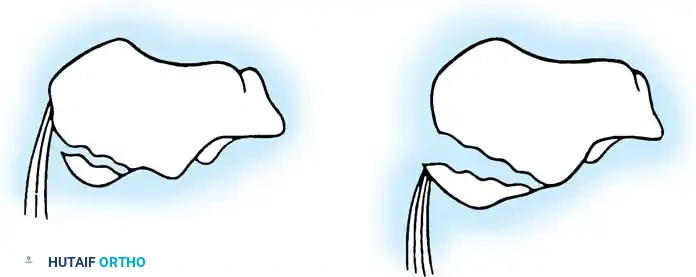

The Primary Fracture Line

This shear force creates the primary fracture line, which is almost universally present. It extends from the proximal, medial aspect of the calcaneal tuberosity, obliquely through the anterolateral wall, typically exiting near the crucial angle of Gissane. The position of this line through the posterior facet is variable; it may occur in the medial third (near the sustentaculum tali), the central third, or the lateral third.

This primary line divides the calcaneus into two main fragments:

1. The Sustentacular (Anteromedial) Fragment: This fragment remains securely attached to the talus via the robust interosseous talocalcaneal and deltoid ligaments. It is considered the "constant fragment" and serves as the foundation for surgical reconstruction.

2. The Tuberosity (Posterolateral) Fragment: This fragment is displaced superiorly, laterally, and into varus by the pull of the Achilles tendon and the impact of the injury.

As the axial force continues, the medial spike of the sustentacular fragment is driven medially, threatening the neurovascular bundle, while secondary fracture lines propagate through the posterior facet.

Essex-Lopresti classically described two distinct patterns based on the exit point of the secondary fracture line:

- Joint Depression Type: The secondary fracture line exits posterior to the posterior facet but anterior to the Achilles tendon insertion. The articular fragment is driven deep into the cancellous body of the calcaneus.

- Tongue Type: The secondary fracture line exits posterior to the Achilles tendon insertion. The posterior facet remains attached to the posterior tuberosity, creating a single, large "tongue" piece that rotates dorsally.